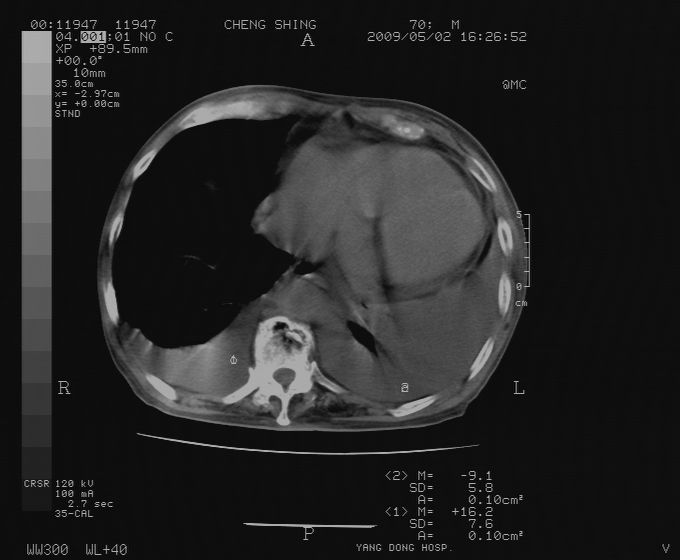

标题: CT19743:男70岁,肺部疾病入院,B超发现肝右叶占位,CT [打印本页]

标题: CT19743:男70岁,肺部疾病入院,B超发现肝右叶占位,CT

肝表面塌陷,病灶周围有子灶,前面较大子灶强化符合肝癌表现,考虑肝癌肝转移可能性大.

1)考虑肝癌并肝内转移。2)少量腹水。3)双侧胸腔积液。

1)考虑肝癌并肝内转移。2)少量腹水及双侧胸腔积液。3)椎体退变。